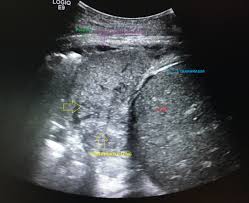

Pleural effusions unlikely associated with ra as transudative, and without monocyte predominance or low glucose. Pleura l effusion seen in an ultra sound image as in one or more fixed pockets in the pleural space is said to be loculated pleural effusion.in. Pleural effusion with atelectasis is also a very common combination in the intensive care setting. Ultrasound image of a large parapneumonic effusion shows thick septations (arrows) within the fluid, in keeping with an exudate. There's always a small amount of liquid within this lining to help lubricate the. Ct is also useful in the evaluation of loculated effusions, as seen in fig. Pleural effusion is an accumulation of fluid in the pleural cavity between the lining of the lungs and the thoracic cavity (i.e., the visceral and parietal pleurae). A video assisted thoracoscopic surgery (vats) with lysis of adhesions is also a viable option for loculated effusions. Accompanying adhesions can be identied. Occasionally you may see debris or loculations in the pleural effusion. A pleural effusion is accumulation of excessive fluid in the pleural space, the potential space that surrounds each lung. Pleural effusion, also called water on the lung, is an excessive buildup of fluid in the space between your lungs and chest cavity. Pleural effusions are produced by a wide variety of causes.

Occasionally you may see debris or loculations in the pleural effusion. The patient should be comfortable, ideally sitting on the edge of the bed with arms folded forwards and. Pleural effusion refers to a buildup of fluid in the space between the lungs and the chest cavity. Whereas, a heterogenous effusion with white septations indicates that it's loculated, and probably exudative. The image below shows an image.